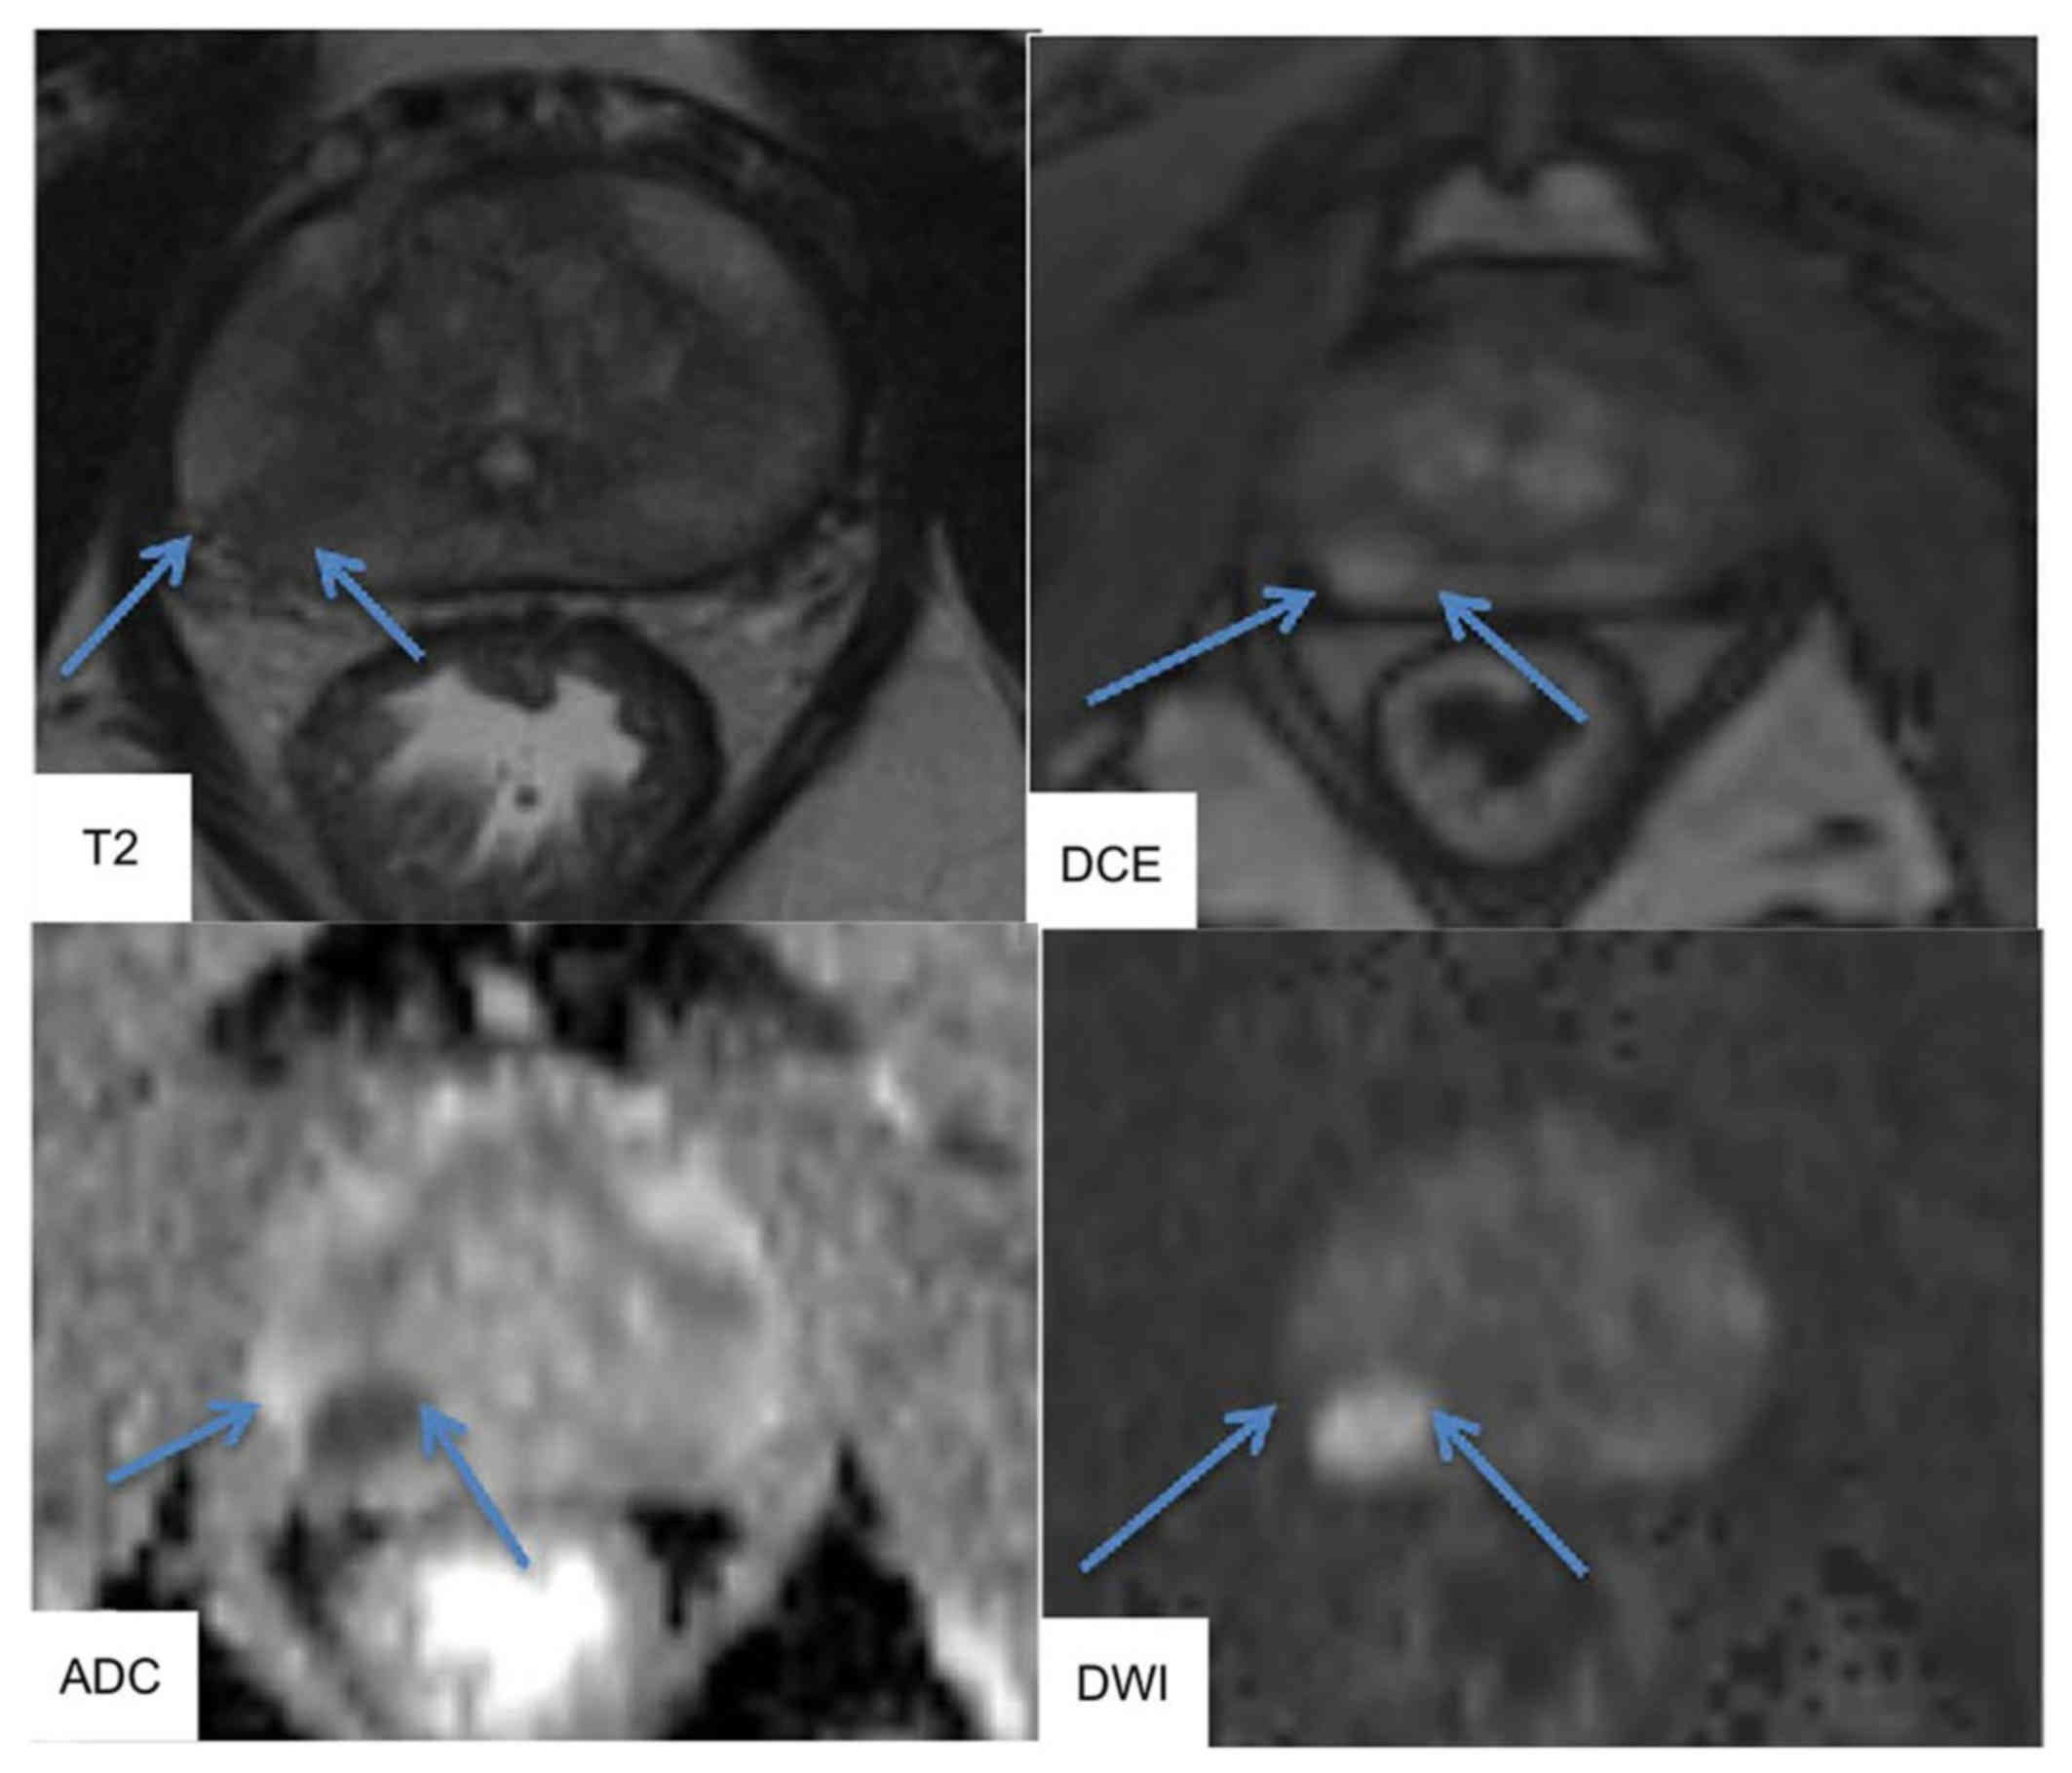

At our institution, the mpMRI system is a 3.0-Tesla scanner (Signa Excite XI 1.5 and 3.0-Tesla, 32-channel torso-array coil). T2-weighted fast spin-echo imaging (T2WI, 3000/120, 4 NEX, 4 min 36 sec, 3.4 mm slice, 0 mm space), diffused-weighted imaging (DWI, single-shot diffusion echo plannar imaging, b=0, 2,000 sec/min2 for whole pelvic, 0, 1,500 sec/min2 for prostate, 4000/69.5 (pelvis), 4000/58.3 (prostate), 1 min 24 sec, 3 min 24 sec), and Gadolinium-dynamic contrast enhanced MRI (DCE, liver imaging with Volume Acceleration-flexible (LAVA-Flex), 4/1.1/12°, 15 sec, 40, 60, and 180 sec after i.v.) were performed. MRI could identify ROIs, and MR images were interpreted by experienced radiologists in accordance with ESUR PI-RADS v2.0. The typical images of mpMRI were shown in Fig. 1. T2WI was used for prostate cancer detection, localization and imaging. T2WI alone was sensitive but not specific for PCa and should be improved using DCE and DWI MRI. DWI allowed apparent diffusion coefficient (ADC) maps to be calculated, enabling qualitative and quantitative assessment of PCa aggressiveness.

Figure 1.

Typical images of multiparametric magnetic resonance imaging. T2-weighted imaging (T2WI) and diffusion-weighted imaging (DWI) were performed using an endorectal coil at a 3.0 tesla scanner. T2WI showed a hypointense area in the right peripheral zone (arrow). DWI and dynamic contrast-enhanced (DCE) were reported to provide higher diagnostic sensitivity. DCE and DWI showed area of rounded hyperintensity (arrow). DWI allowed apparent diffusion coefficient (ADC) maps to be calculated. The ADC map depicted a cancer focus in the right peripheral zone as a hypointense are (arrow).